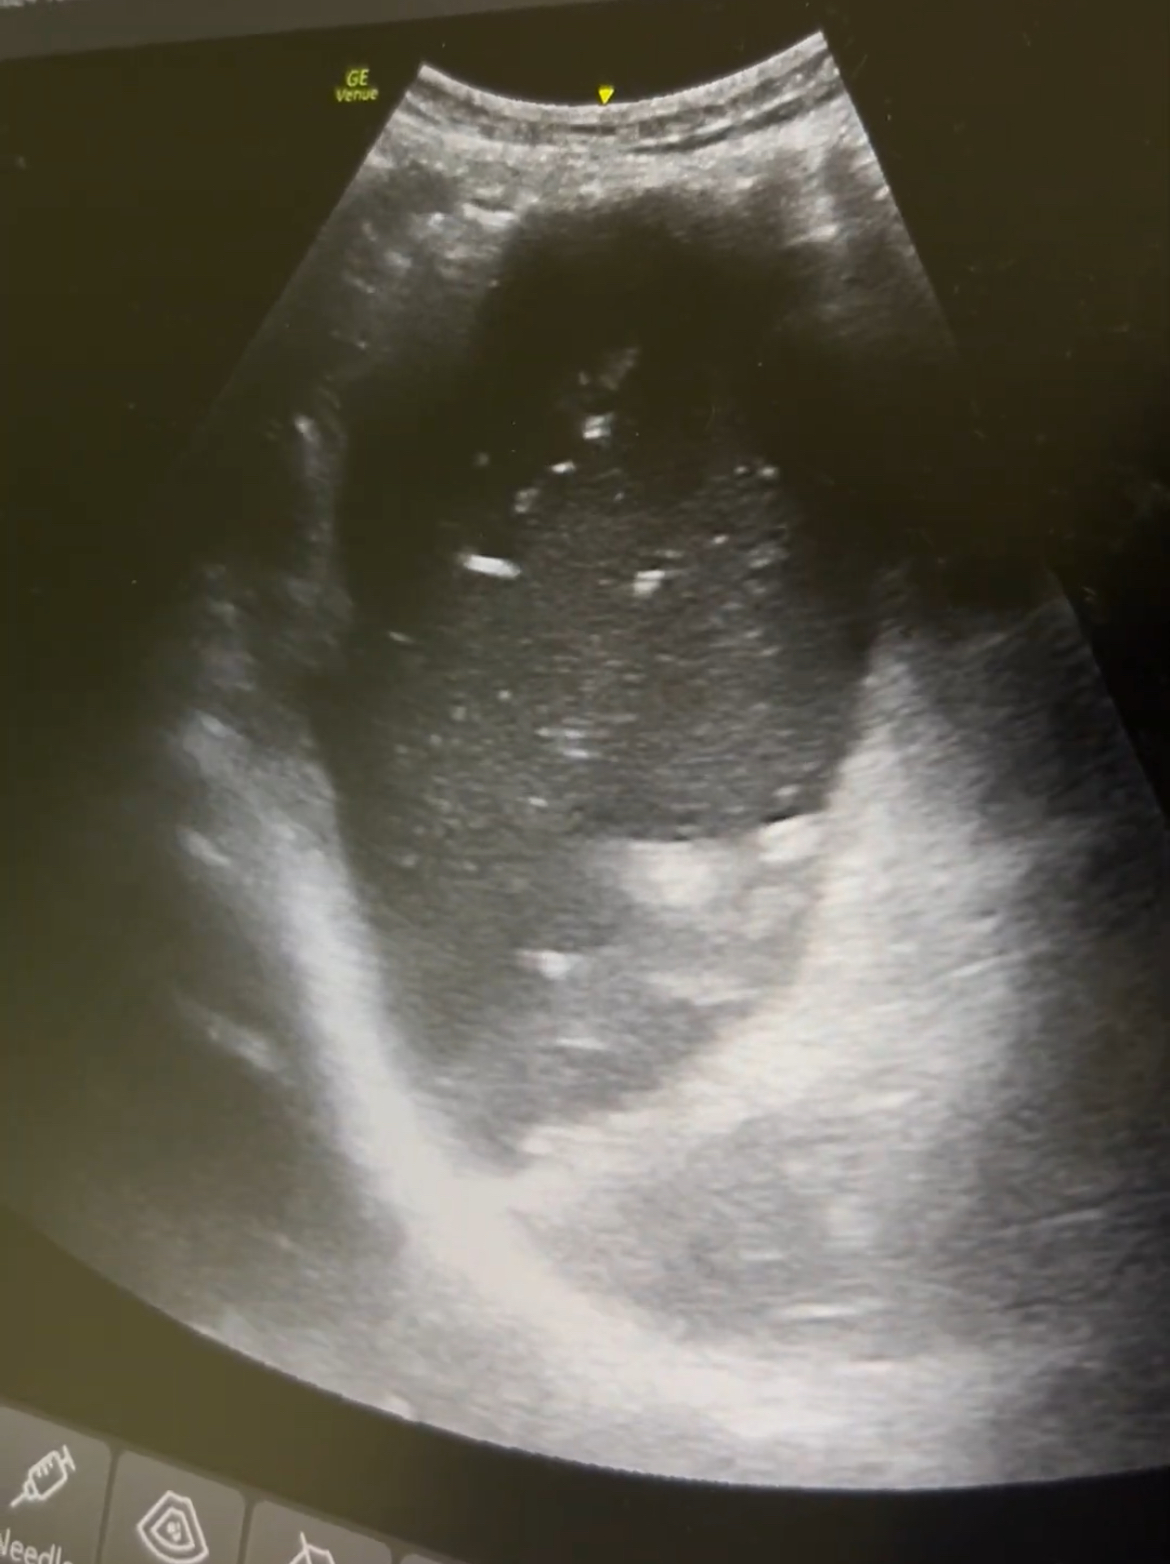

Ante AP de cirugía, dolor abdominal y vómitos, se realiza rx abdominal que resulta normal. Dada la alta sospecha, se realiza ecografía: gran cámara gástrica con contenido en su interior con dinámica «en lámpara de lava». Además, asas de intestino delgado dilatadas (diámetro 2,9 cm) con movimiento de peristalsis y rebote y edema de pared. Compatible con obstrucción intestino delgado.

Utilidad de ecografía abdominal en el ámbito de Urgencias hospitalarias o de Atención Primaria ante dolor abdominal agudo, en concreto para diagnóstico de obstrucción intestinal ante la sospecha y falta de radiografía simple de abdomen o ausencia de hallazgos sugestivos de la misma en la Rx abdominal simple y alta sospecha clínica.